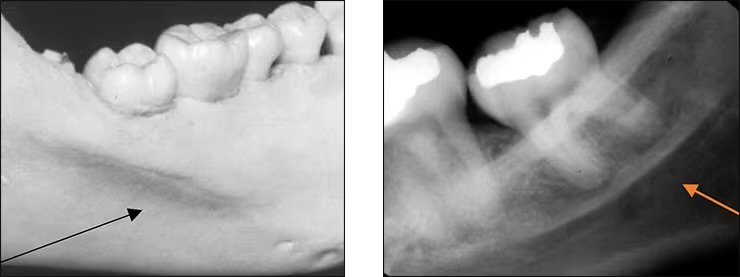

Mental foramen

Located below roots of mandibular premolars.

Is the opening for passage of the mental nerve and vessels.

Often misinterpreted as periapical lesions